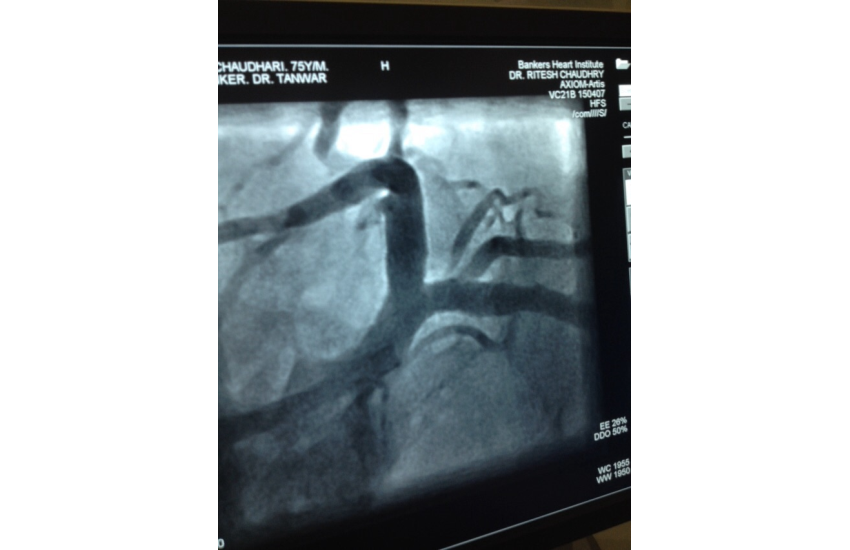

75 years old male presented with unstable angina undergone CAG which is shown LMCA bifurcation lesion first option given for CABG surgery but Pt. is not willing for that so after discussing all the risk of LMCA bifurcation kissing steanting Than patient and relatives ready for that and with all life support system successfully done by Dr N T sir. After steanting patient is doing well.